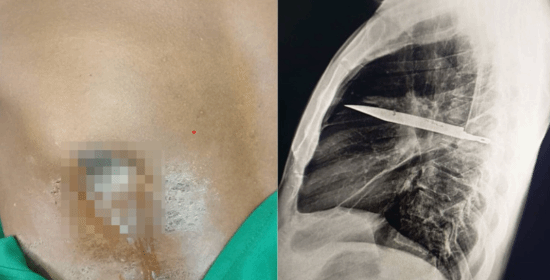

醫生隨即安排胸腔X光檢查。畫面清楚顯示,右肩胛骨位置有一片利刃狀金屬殘留物,從肩胛骨方向刺入胸腔,周圍被膿液與壞死組織包圍,顯示已存在相當長一段時間。

進一步評估后,醫生研判這片刀刃極可能是當年沖突時遺留在體內,時間約8年。之所以沒有立刻要命,是因為刀刃位置非常剛好,避開了心臟、大血管與主要肺部結構,才讓男子這么多年來幾乎毫無異狀。

在醫生安排下,男子立刻接受外科手術,將胸腔內的刀片完整取出,同時清除周邊壞死組織與膿液。